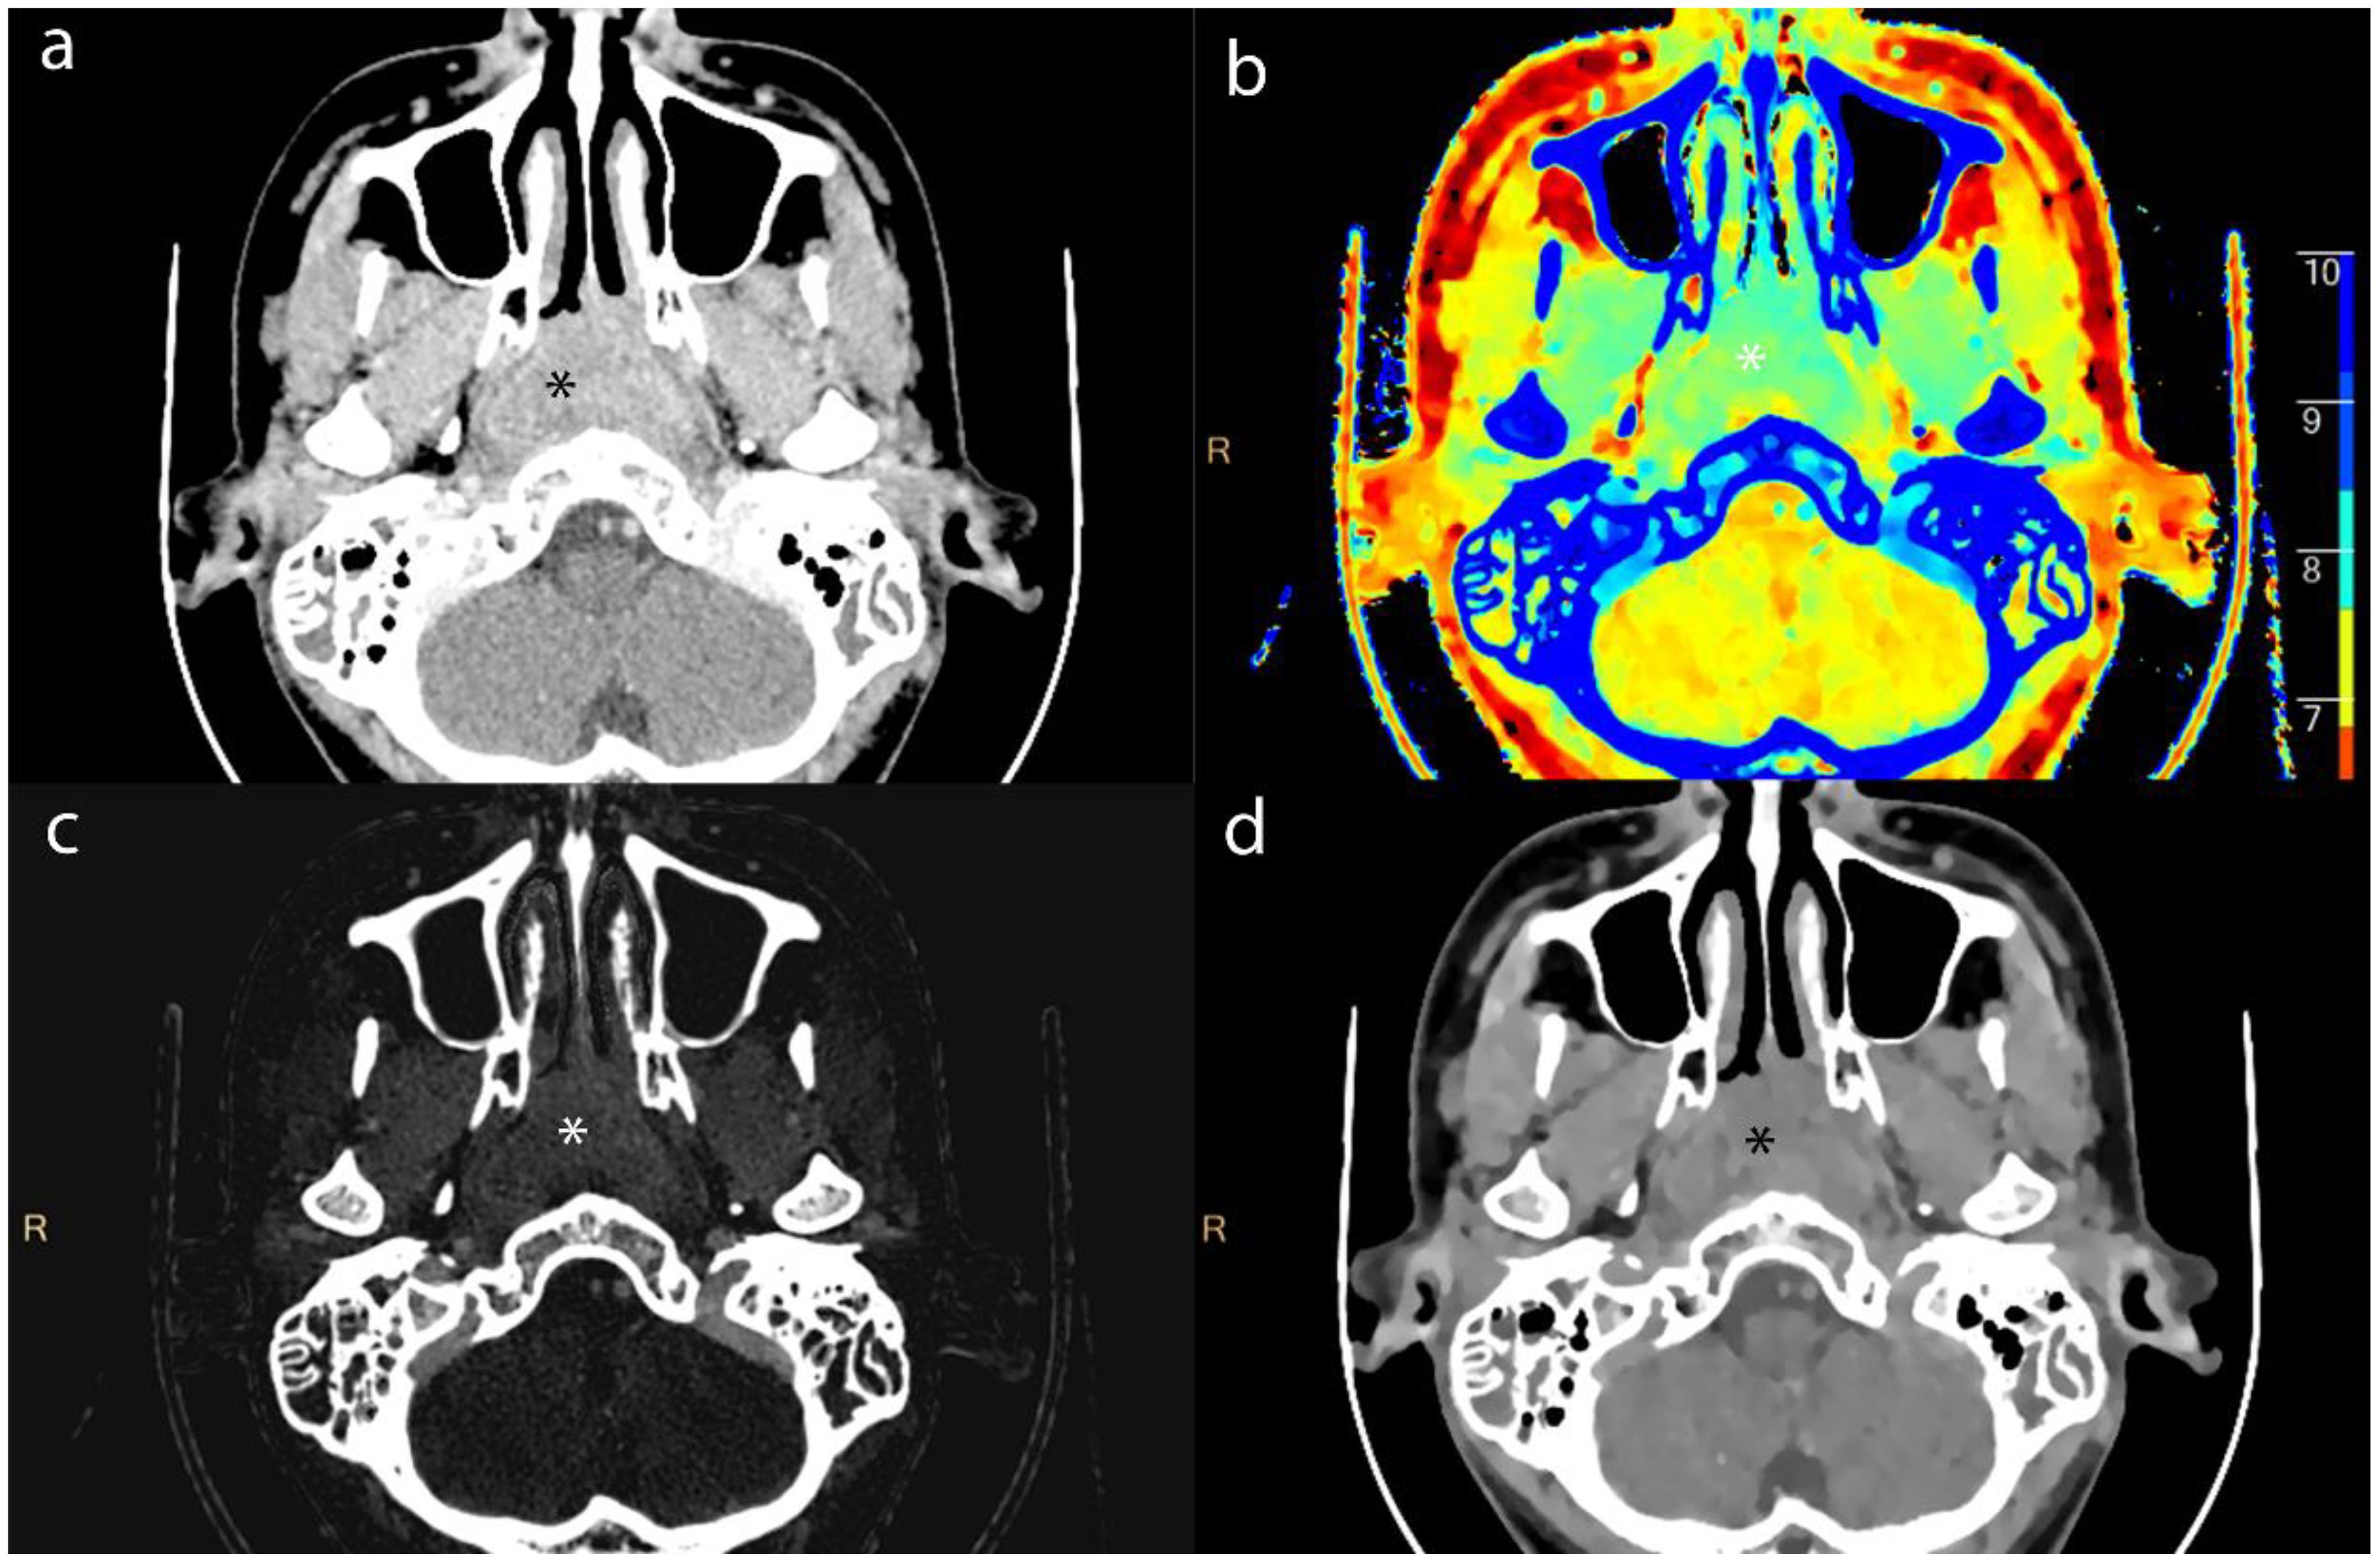

Purpose: To explore the value of dual-energy CT (DECT) in evaluating the efficacy of nasopharyngeal carcinoma (NPC) and in the detection of metastatic lymph nodes (MLNs). Materials and Methods: For this retrospective study, we collected and analyzed clinical and imaging data from 83 patients diagnosed with NPC via histopathology, who were admitted to the Radiotherapy Department from August 2022 to July 2024. The cohort consisted of 64 males and 19 females, with an average age of 50.86±13.45 (years). All patients underwent DECT enhancement and MRI scanning before and after the first treatment course to assess the extent of lesions and lymph nodes (LNs). A total of 423 LN imaging datasets were analyzed. We measured iodine concentration (IC), effective atomic number (Zeff), electron density (ED), and normalized iodine concentration (NIC). Additionally, we recorded the magnetic resonance ADC values of the LNs. Results: Statistical analysis of Zeff, ED, and NIC values of lesion and LNs revealed no significant differences between groups (p > 0.05). The Zeff, ED, and NIC values for lesions and LNs were significantly lower after treatment than before (p < 0.05). Receiver operating characteristic (ROC) analysis for MLNs indicated that the area under the ROC curve (AUC) for NIC indicated high accuracy. Conclusion: DECT provides valuable functional parameters for assessing the efficacy of NPC and demonstrates significant clinical application value. Notably, the NIC parameter shows high diagnostic efficacy for MLNs, comparable to the ADC value obtained from MRI.